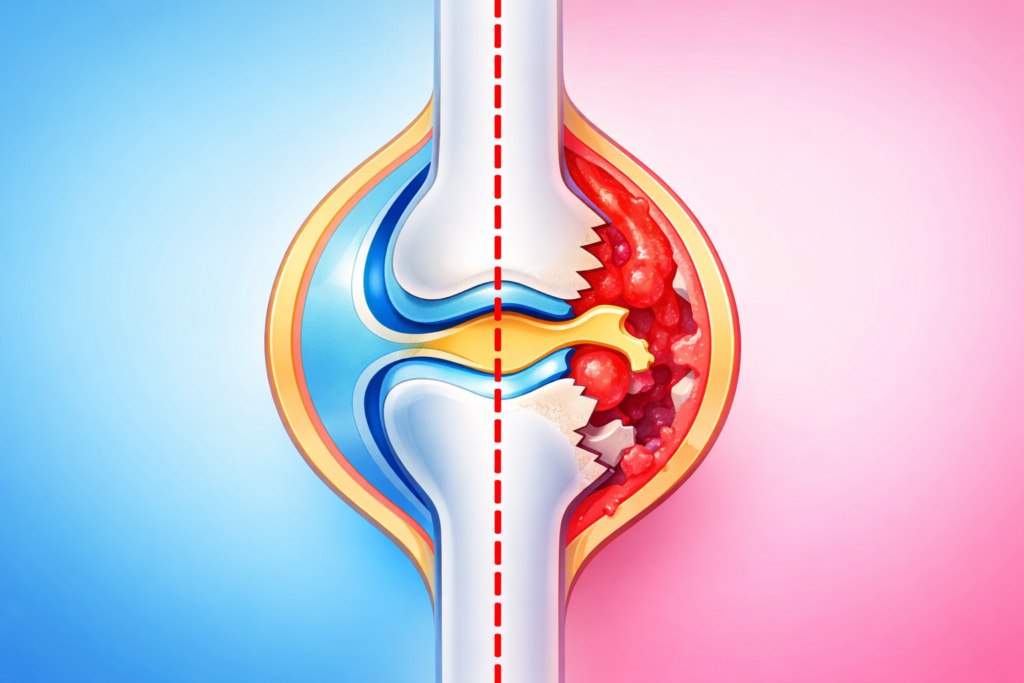

関節リウマチは、免疫の異常によって自分自身の関節を攻撃してしまう「自己免疫疾患」のひとつです。

本来、免疫は細菌やウイルスなどの外敵から体を守るための仕組みですが、関節リウマチではこの免疫が誤作動を起こし、関節の滑膜(かつまく)という組織に炎症を引き起こします。

その結果、関節の腫れや痛みが慢性的に続き、進行すると骨や軟骨が破壊され、関節の変形や機能障害を起こすことがあります。